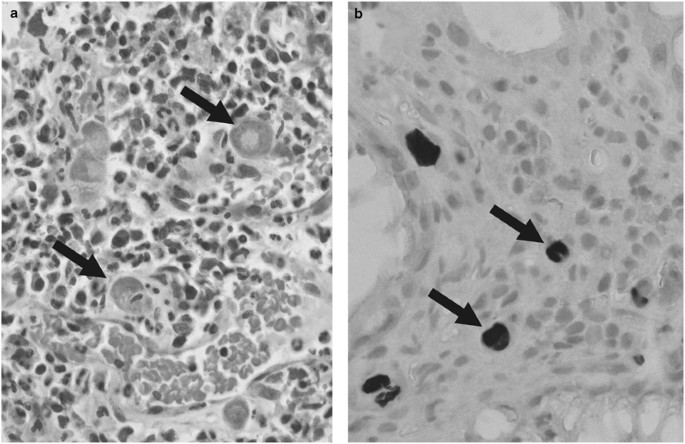

Generally, viral loads showed a broad variation ranging from 5 copies/105 cells to 8.7 × 105 copies/105 cells. The mean viral load covering all cytomegalovirus positive samples was approximately 37 400 (±1.50 × 105) cytomegalovirus copies/105 cells and the median was 900 cytomegalovirus copies/105 cells (Figure 1a). Regarding the total distribution of viral loads, with 13 patients (35%) the majority showed viral loads of <100 cytomegalovirus copies/105 human cells. Six patients (16%) displayed viral loads ranging between 100 and 1000, 11 patients (30%) had 1000–10 000 cytomegalovirus copies/105 cells, 5 patients (14%) had viral loads between 10 000 and 100 000 cytomegalovirus copies/105 cells and 2 patients (5%) revealed >100 000 cytomegalovirus copies/105 cells (Figure 1b). For assay control, a panel composed of 21 cytomegalovirus-negative control samples was analyzed. In none of these, cytomegalovirus DNA could be detected (data not shown). By histological evaluation only in tissue sections with exceptionally high viral loads such as 8.9 × 105 copies/105 cells cytomegalovirus infection could be confirmed by the presence of typical inclusion bodies (owl’s eyes) as shown in Figure 2a and Table 2.

Histological detection of cytomegalovirus infection. (a) Detection of viral inclusion (indicated by black arrows) using hematoxylin and eosin-stained tissue sections. (b) Detection of cytomegalovirus infection by immunohistochemistry. A colon tissue section stained with a monoclonal antibody directed against cytomegalovirus is shown. Immunohistochemistry-positive cells are indicated by arrows.